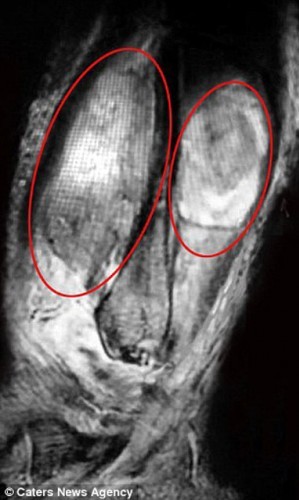

19 yaşındaki kızın iddiasına göre doktorlar emara göndermedi. 24 kez doktora gittikten sonra emar çekilince bacağında Ewing Sarkomu da denilen kötü huylu kemik tümörü olduğu ortaya çıktı. Üstelik bacağındaki kanser akciğerine ve kasığına kadar yayılmıştı.

Natalie'nin tümörü o kadar büyüktü ki amputasyondan başka çaresi yoktu. Bacağının dizden aşağısı kesilen genç kız protezle yürümeyi öğrendi. Uzun süren kemoterapinin ardından saçları tekrar uzamaya başladı.